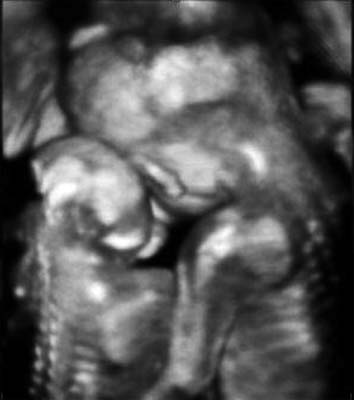

Fig 2

A three-dimensional ultrasound image demonstrates that the normal fetus put his arms around the shoulders of the other fetus with anencephaly and leaned against him at 22 weeks of gestation.

A 29-year-old pregnant woman with parity 0-0-0-0 visited the hospital at 14 weeks after spontaneous pregnancy. Abdominal 2D ultrasound (Voluson E8, GE Healthcare, USA) revealed that the first twin was within the normal ranges for the gestational age but the second twin showed anencephaly. There was one placenta and no amniotic membrane separated the two fetuses, and both were male. Umbilical cord entanglement was observed by using 3D ultrasound (Voluson E8, GE Healthcare, USA) (Fig. 1). The parents received counseling regarding monoamniotic twin pregnancy, anencephaly of a fetus and complications of umbilical cord entanglement. The patient underwent weekly prenatal medical examinations at the outpatient clinic. A fetal ultrasound conducted at 22 weeks did not show any abnormal finding except for one fetal anencephaly (Fig. 2). Starting from 26 weeks, a Doppler study of the umbilical cord and a non-stress test were performed every week and their results were within normal ranges. Also, amniotic fluid index (AFI) was checked every week, polyhydramnios (AFI = 25) was detected at 26 weeks and persisted until delivery (AFI: 20 ~ 28). The polyhydramnios was asymptomatic and was not treated. Although hospitalization for intensive observation was recommended at 30 weeks of pregnancy, the patient refused such treatment. While she was examined as an outpatient, preterm labor occurred at 33+5 weeks and she was subsequently hospitalized.